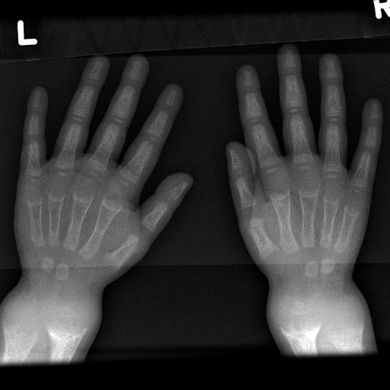

تميل الأشعة السينية أو التصوير الشعاعي لمريض متقدم يعاني من الكساح إلى الظهور بطريقة كلاسيكية: الأرجل المنحنية (الانحناء الخارجي لعظم الساق الطويلة) والصدر المشوه. تحدث التغييرات في الجمجمة أيضًا مما يؤدي إلى ظهور "رأس مربع" مميز يُعرف باسم "caput quadratum".[15] تستمر هذه التشوهات في سن البلوغ إذا لم يتم علاجها تشمل العواقب طويلة المدى التقوس الدائم أو تشوه العظام الطويلة والظهر المنحني[16]

- يظهر التصوير الشعاعي عادة اتساع مناطق التكلس المؤقت للكراديس الثانوية للعظم غير المعدني. عادة ما تظهر التجلف ، والابلاء ، والتفلطح في الكراديس مع النمو وتحمل الوزن المستمر.[37] تُرى هذه التغييرات في الغالب في مواقع النمو السريع ، بما في ذلك عظم العضد القريب ، والزند البعيد ، وعظم الفخذ البعيدة وكل من الظنبوب الداني والبعيدة. لذلك ، يمكن إجراء مسح للهيكل العظمي للكساح باستخدام الصور الشعاعية الأمامية الخلفية للركبتين والمعصمين والكاحلين.[37]